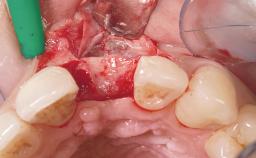

Late Flapless Placement of an Implant in a Maxillary Left Central Incisor Site

A 39-year-old male patient presented with a chief complaint of discomfort and gingival discoloration around his maxillary left central incisor. He was in good general health and was a non-smoker. His past dental history was significant because of the traumatic fracture of tooth 21 in a sporting accident at age 13. Initial dental treatment included endodontic therapy and a full-coverage restoration. The patient became symptomatic 5 years later, when structural failure of the tooth resulted in the dislodgment of the crown. Endodontic retreatment, apical surgery, and post-and-core restoration were performed.